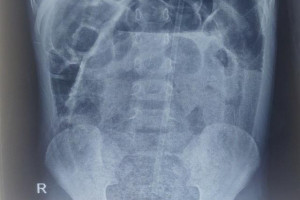

Mới đây, hình ảnh chụp X-quang phổi của những bệnh nhân mắc COVID-19 được đưa ra so sánh với hình chụp X-quang của những người hút thuốc lá và người khỏe mạnh. Hình ảnh cho thấy phim chụp của bệnh nhân COVID-19 bị đục và tổn thương nặng hơn rất nhiều so với những người hút thuốc lá lâu năm.

Brittany Bankhead Kendall – phó giáo sư phẫu thuật tại Đại học Công nghệ Texas, Mỹ – cho rằng, phim chụp X-quang phổi giống như một bộ phim đen trắng: Xương, các cơ quan và cơ xung quanh phổi của những người khỏe mạnh có màu trắng, và những phần còn lại có màu đen. Nhiều chất khác nhau có thể chiếm không gian phổi, bao gồm chất lỏng, cục u, sẹo mô hoặc các vật thể khác, sẽ được thể hiện thành màu trắng trên phim X-quang tùy theo mật độ của chúng. Ung thư phổi, suy tim sung huyết, bệnh viêm phổi thông thường và viêm phổi do vi rút corona đều có thể gây ra hiện tượng này.

Theo thống kê, sau khi vi rút corona gây tổn thương phổi, khoảng 50% -80% phim chụp X quang phổi của bệnh nhân đều có độ mờ đục cao. Theo các báo cáo lâm sàng hiện có, bệnh nhân COVID-19 thường bị tổn thương phổi 1 thời gian dài sau khi nhiễm vi rút. Một số người đã hồi phục, cảm thấy hài lòng vì bản thân không gặp bất kỳ vấn đề gì, nhưng phim chụp X-quang phổi thì lại phát hiện ra những bất thường do di chứng bệnh để lại.

So sánh hình ảnh chụp X-quang phổi của người hút thuốc và bệnh nhân bị nhiễm COVID-19, người ta thấy rằng, phim X-quang của người hút thuốc có đầy sẹo và vệt trắng ở phổi, trong khi hình của bệnh nhân COVID cũng có hình dạng sẹo tương tự nhưng số lượng nhiều hơn và lan khắp phổi. Vì vậy, tình trạng phổi của bệnh nhân COVID thậm chí tồi tệ hơn ở những bệnh nhân hút thuốc lâu năm.